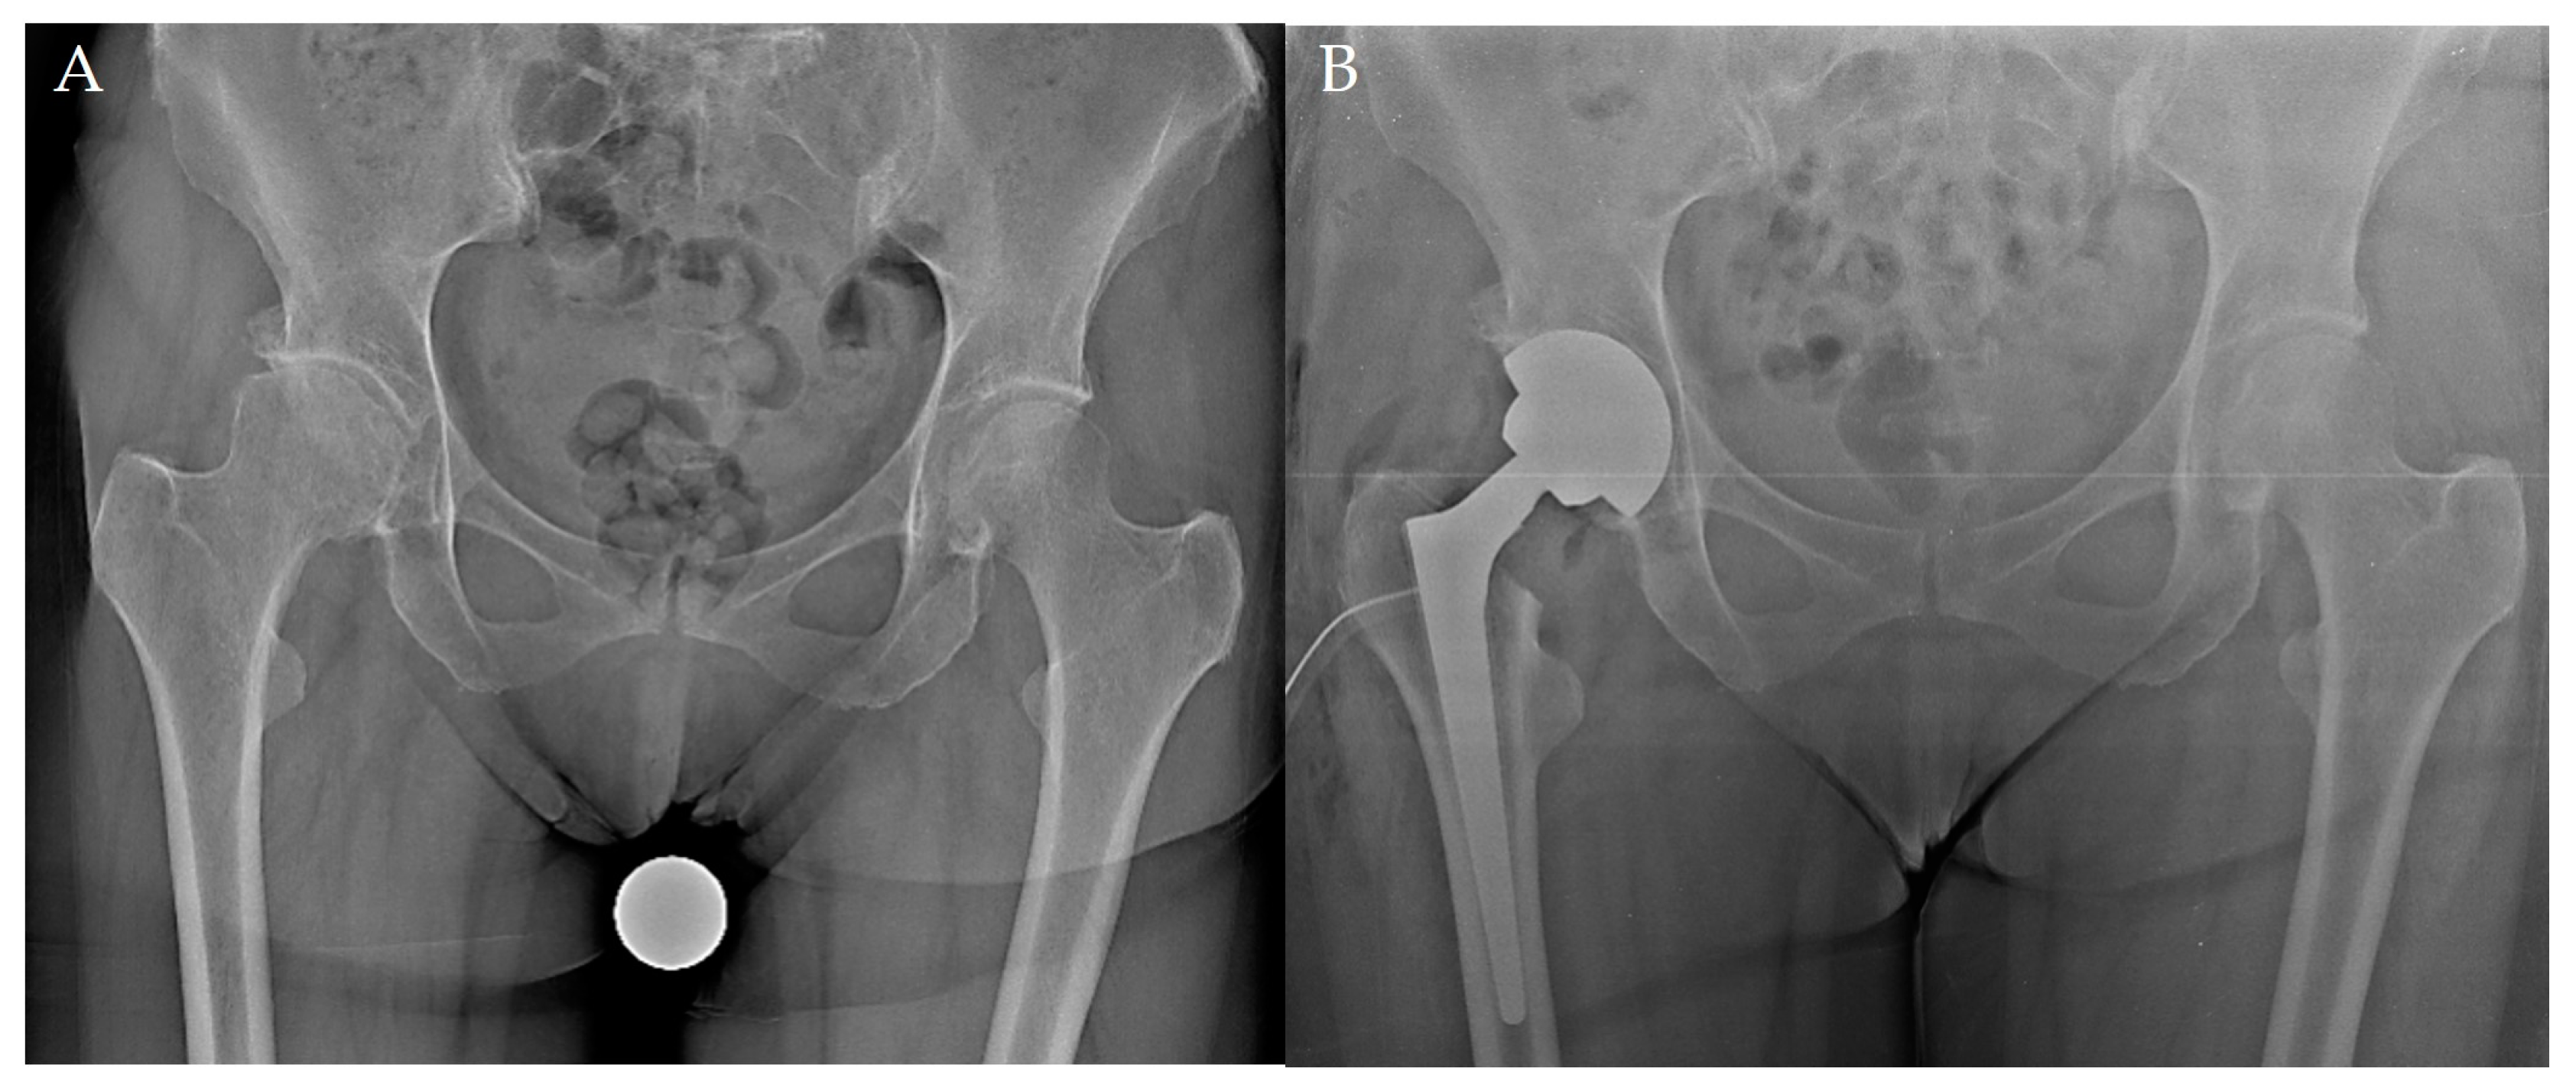

Wagner Cone is a cementless STCTS introduced on the market in 1992 that was slightly modified in 2006 [7,14,22]. The titanium–aluminum–niobium alloy (PROTASUL-100) stem has a tapered angle of 5°, with eight longitudinal sharp ribs; this design allows for an independent tuning of the femoral antetorsion, while providing proximal diaphyseal fixation and rotational stability [7,14,22]. The proximal biomechanics are designed for dysplastic cases, with reduced femoral offset and two neck-shaft angles—125° and 135°; for both the versions, 12 diameters (from 13 to 24 mm) are available [7,14,22] (Figure 1).

Figure 1. The post-operative radiograph of a Wagner Cone stem (B) implanted in a 52-year-old female with primary hip osteoarthritis (A).